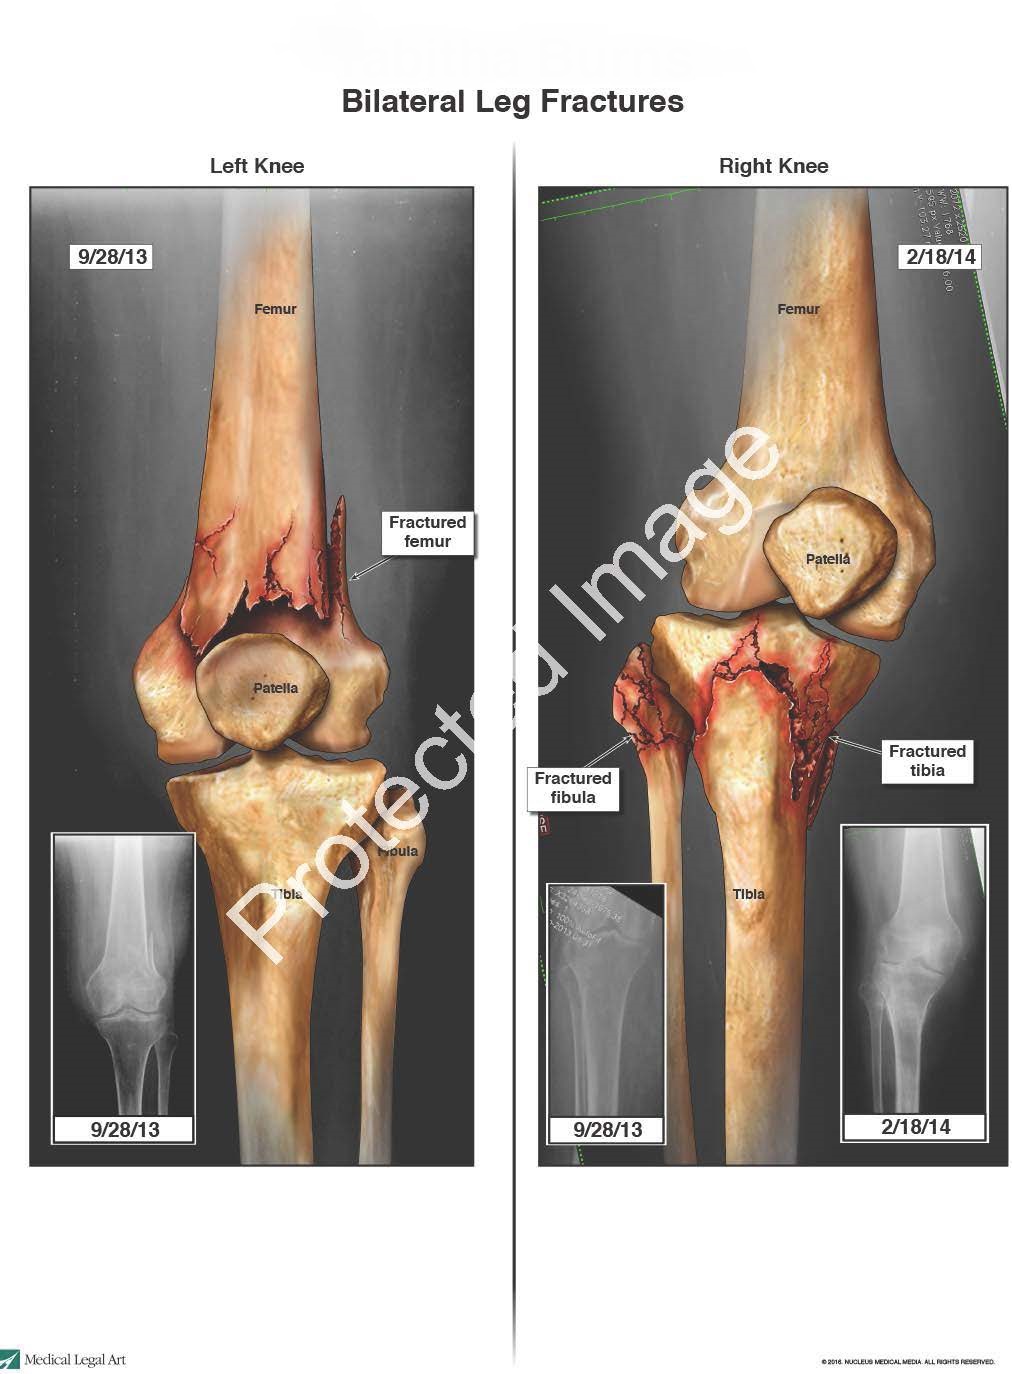

The nursing home staff waited for almost 24 hours after the fall before obtaining mobile x-rays of the patient’s legs. The x-rays revealed an impacted metaphyseal fracture of the distal left femur and left proximal fibular fracture. The patient was transferred to the hospital, where additional x-rays confirmed an impacted, oblique, comminuted fracture of the left femur. Because the patient was non-ambulatory at baseline, her left leg was placed in a knee immobilizer and she was returned to the nursing home, where PT was consulted to increase range of motion to her left leg and decrease her complaints of pain.

The patient continued to complain of pain in both legs, for which she required Morphine, Percocet, and Dilaudid. On February 18, 2014, in response to the patient’s persistent complaints of severe pain in her right knee, mobile x-rays were done that revealed an ongoing angulated fracture of the right proximal tibia and fibula.